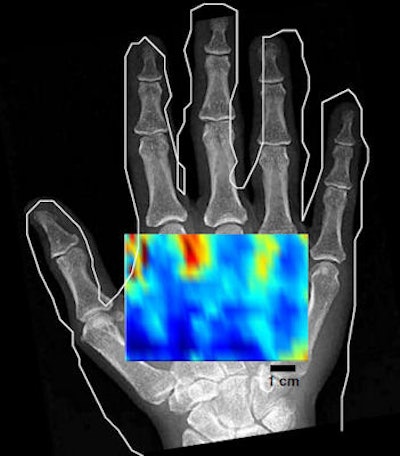

After beam characterization and transmission measurements, images of a phantom and a hand were acquired in vivo using the transducer and a broadband microphone receiver. An image of three 3-mm wooden rods in a water phantom, scanned axially, demonstrated the tomographic reconstruction approach, albeit with some image distortion and artifacts. In vivo noncontact imaging of a hand was demonstrated with a conventional C-mode approach that produces images for a fixed depth below the skin. The low-resolution scan shows varying contrast between the anatomy containing mainly bone and that containing only soft tissue.